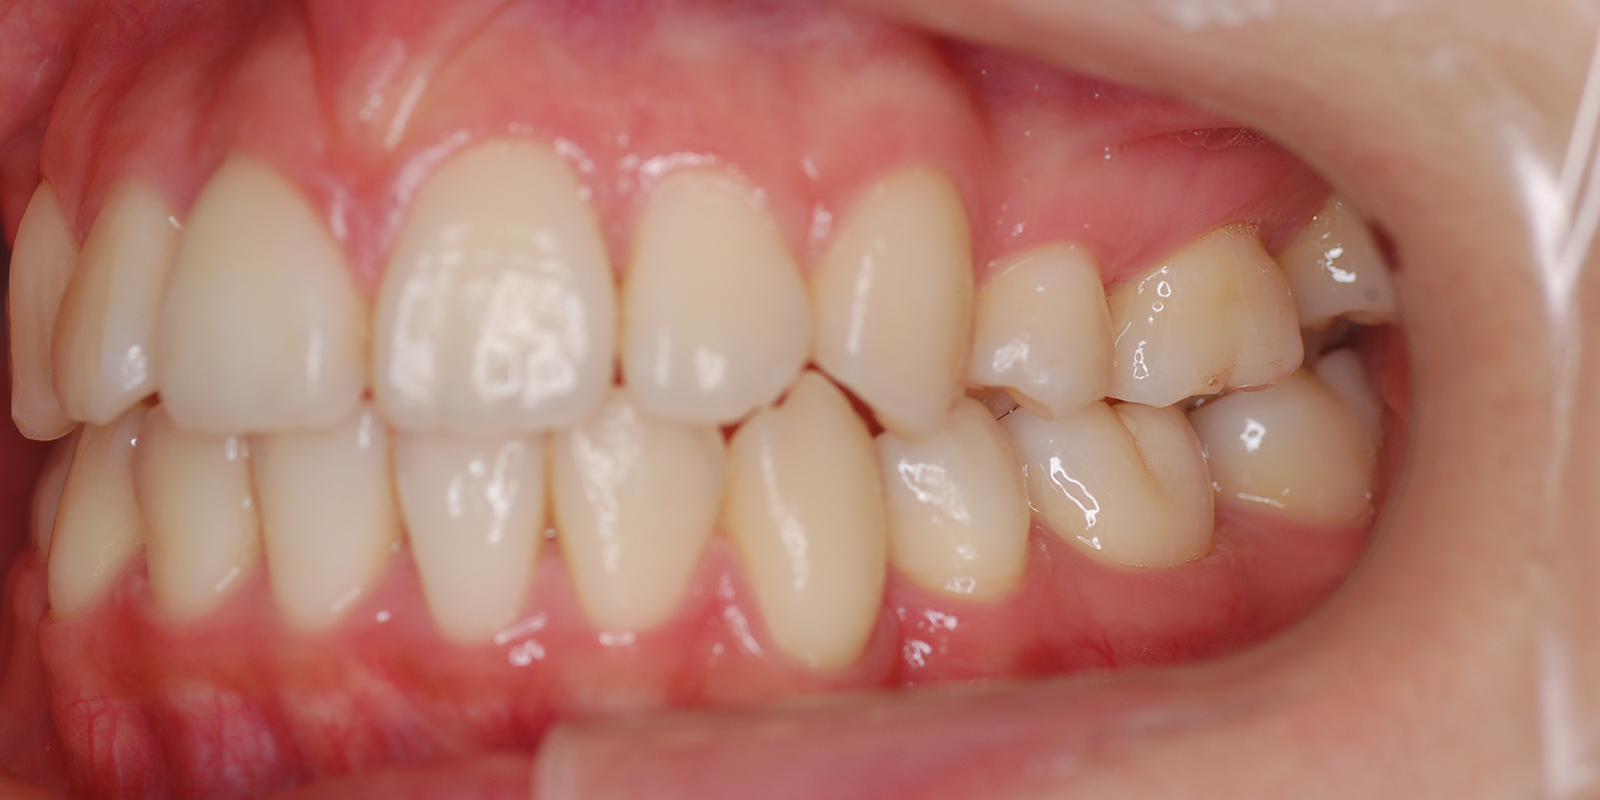

術後

| 主訴 | 噛み合わせが深い |

| 診断 | アングルⅡ級2類Deep bite |

| 初診時年齢 | 8歳3か月 |

| 装置 | EF |

| 抜歯・非抜歯 | 非抜歯 |

| 治療期間 | 2年 |

| 通院回数 | 約12回 |

| 治療費 | 25万円 矯正歯科治療は公的医療保険の適用外の自費(自由)診療となります |

| 治療のリスク | ・装置を使用しなければ効果が出ない ・上下前歯に痛みが出ることがある ・取り外しのためなくすことがある |